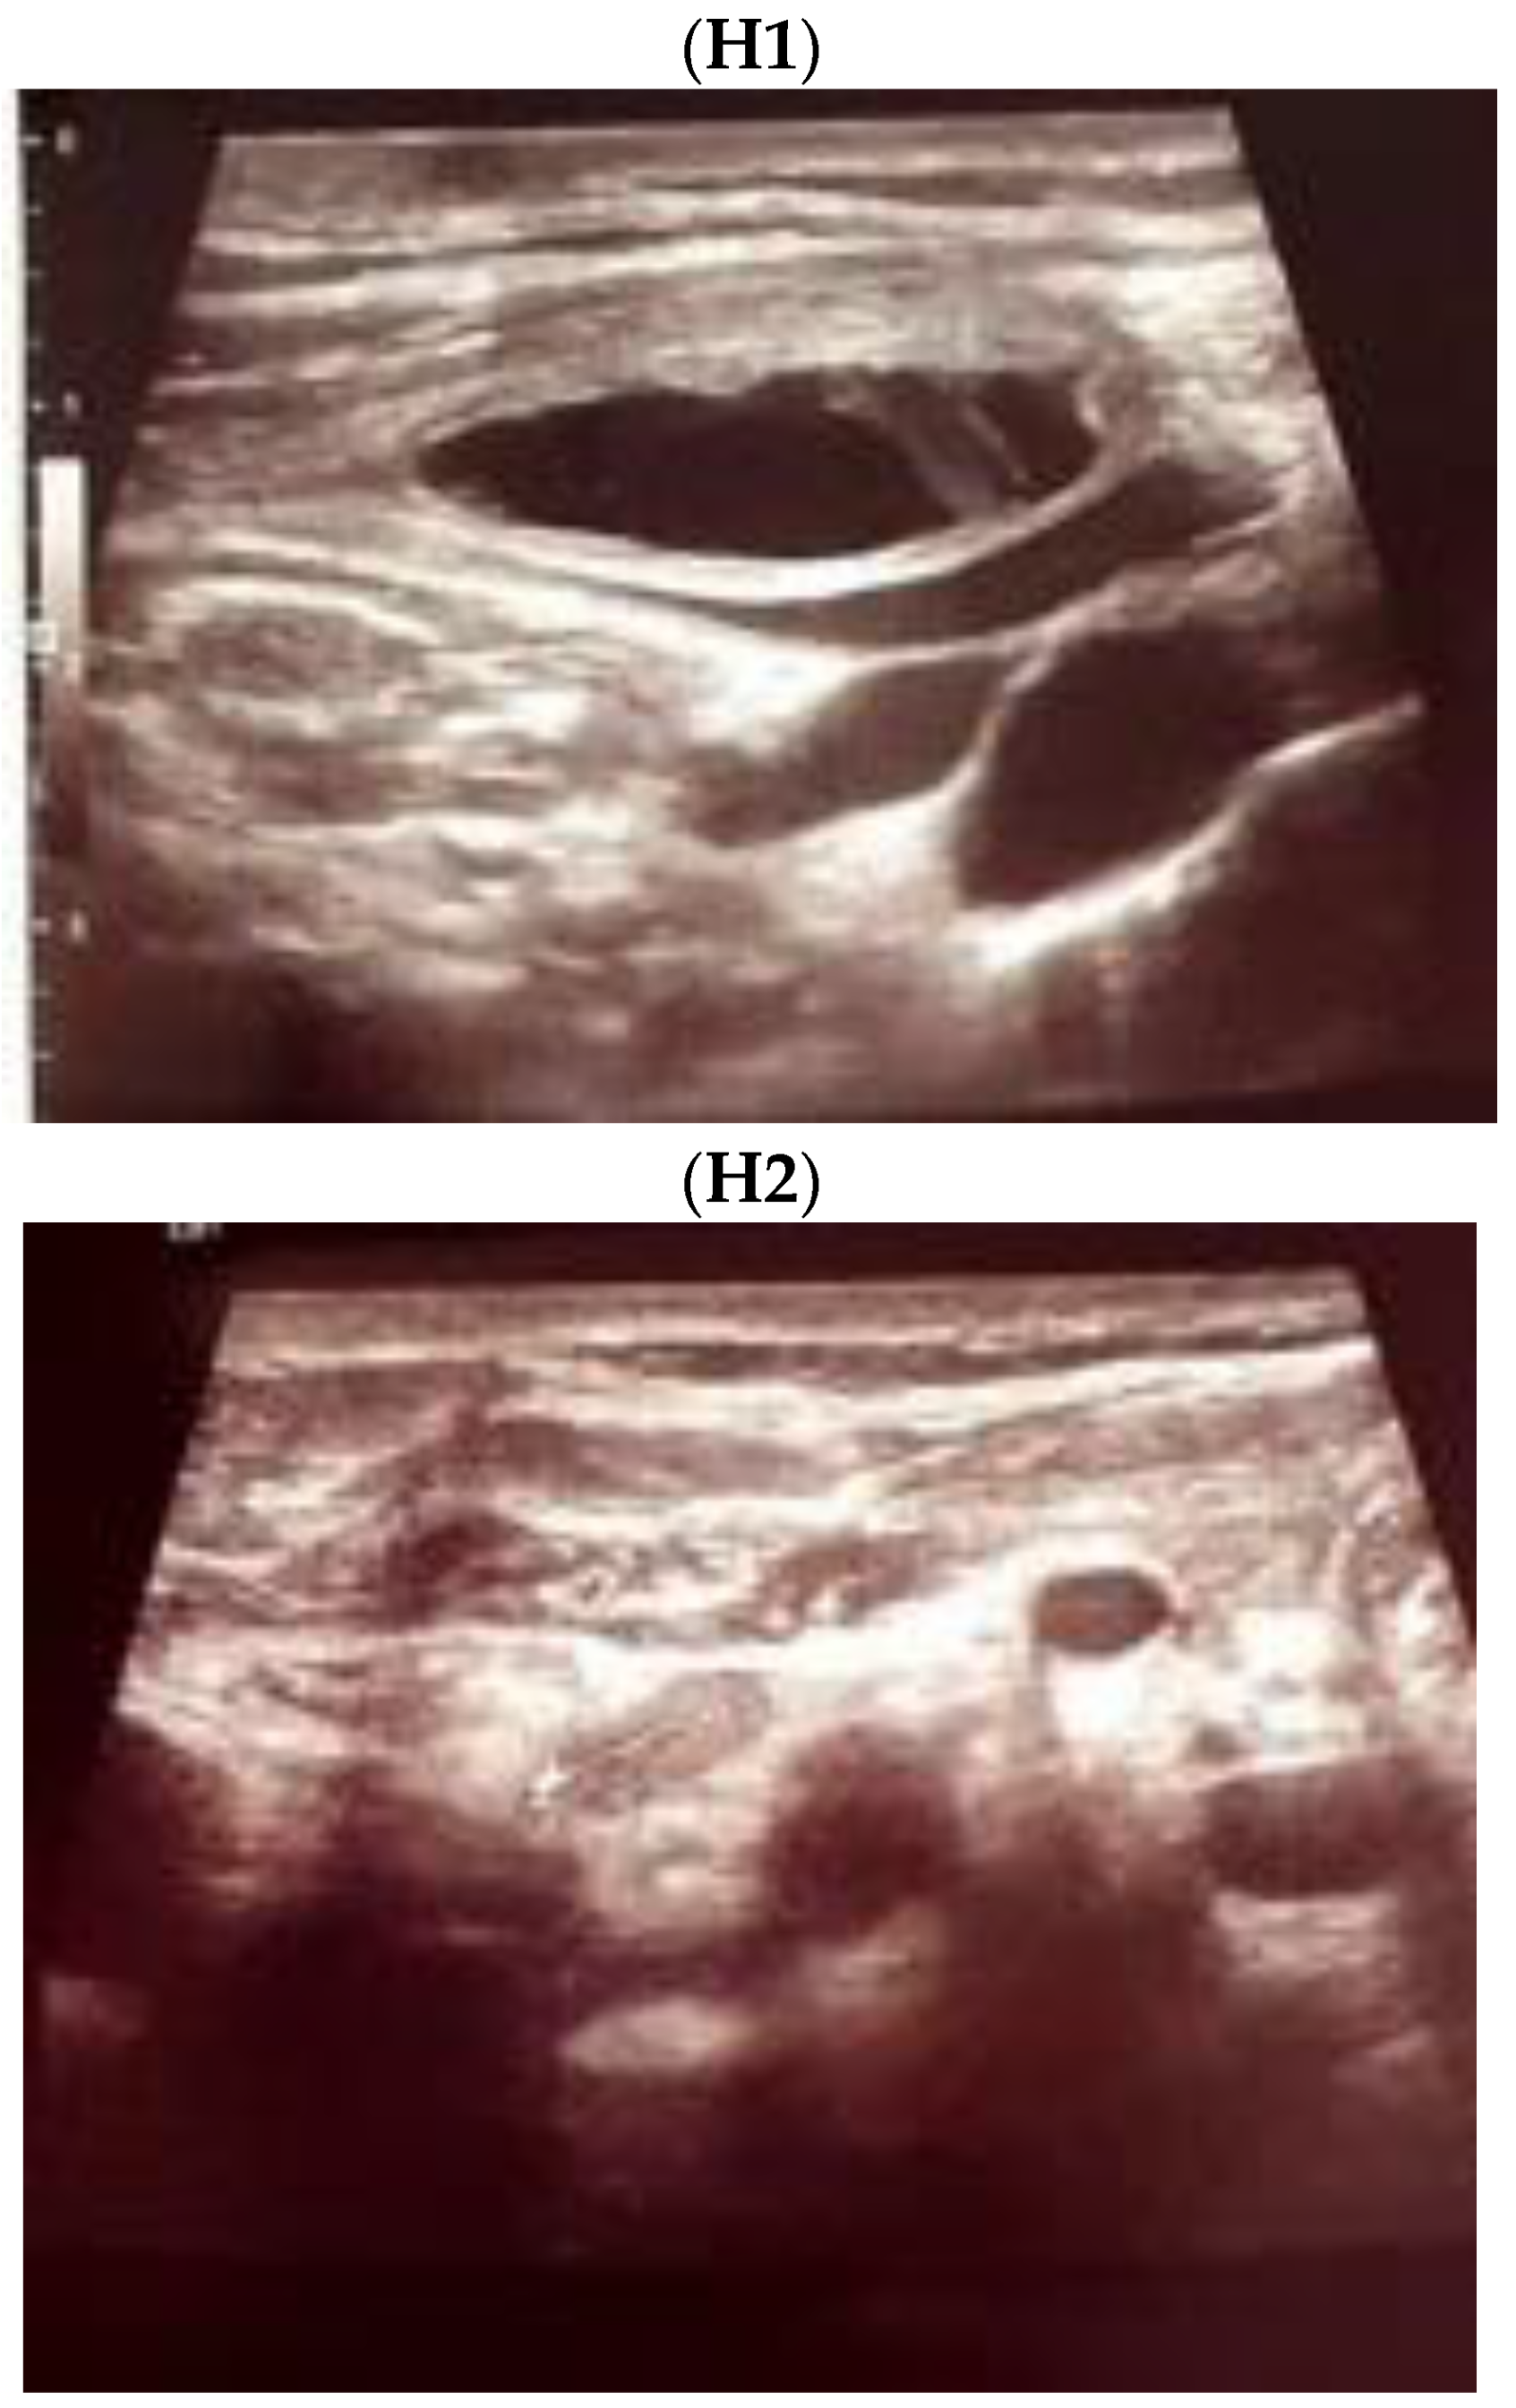

3.2. Thyroidectomy/Lymph Nodes Dissection and Lymphocele/Chylous Leakage

3.3. Post-Thyroidectomy HS and Lymphocele